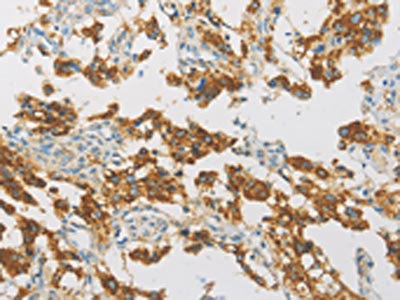

The image on the left is immunohistochemistry of paraffin-embedded Human brain tissue using CSB-PA952993(IDH3G Antibody) at dilution 1/30, on the right is treated with fusion protein. (Original magnification: ×200)

The image on the left is immunohistochemistry of paraffin-embedded Human thyroid cancer tissue using CSB-PA952993(IDH3G Antibody) at dilution 1/30, on the right is treated with fusion protein. (Original magnification: ×200)